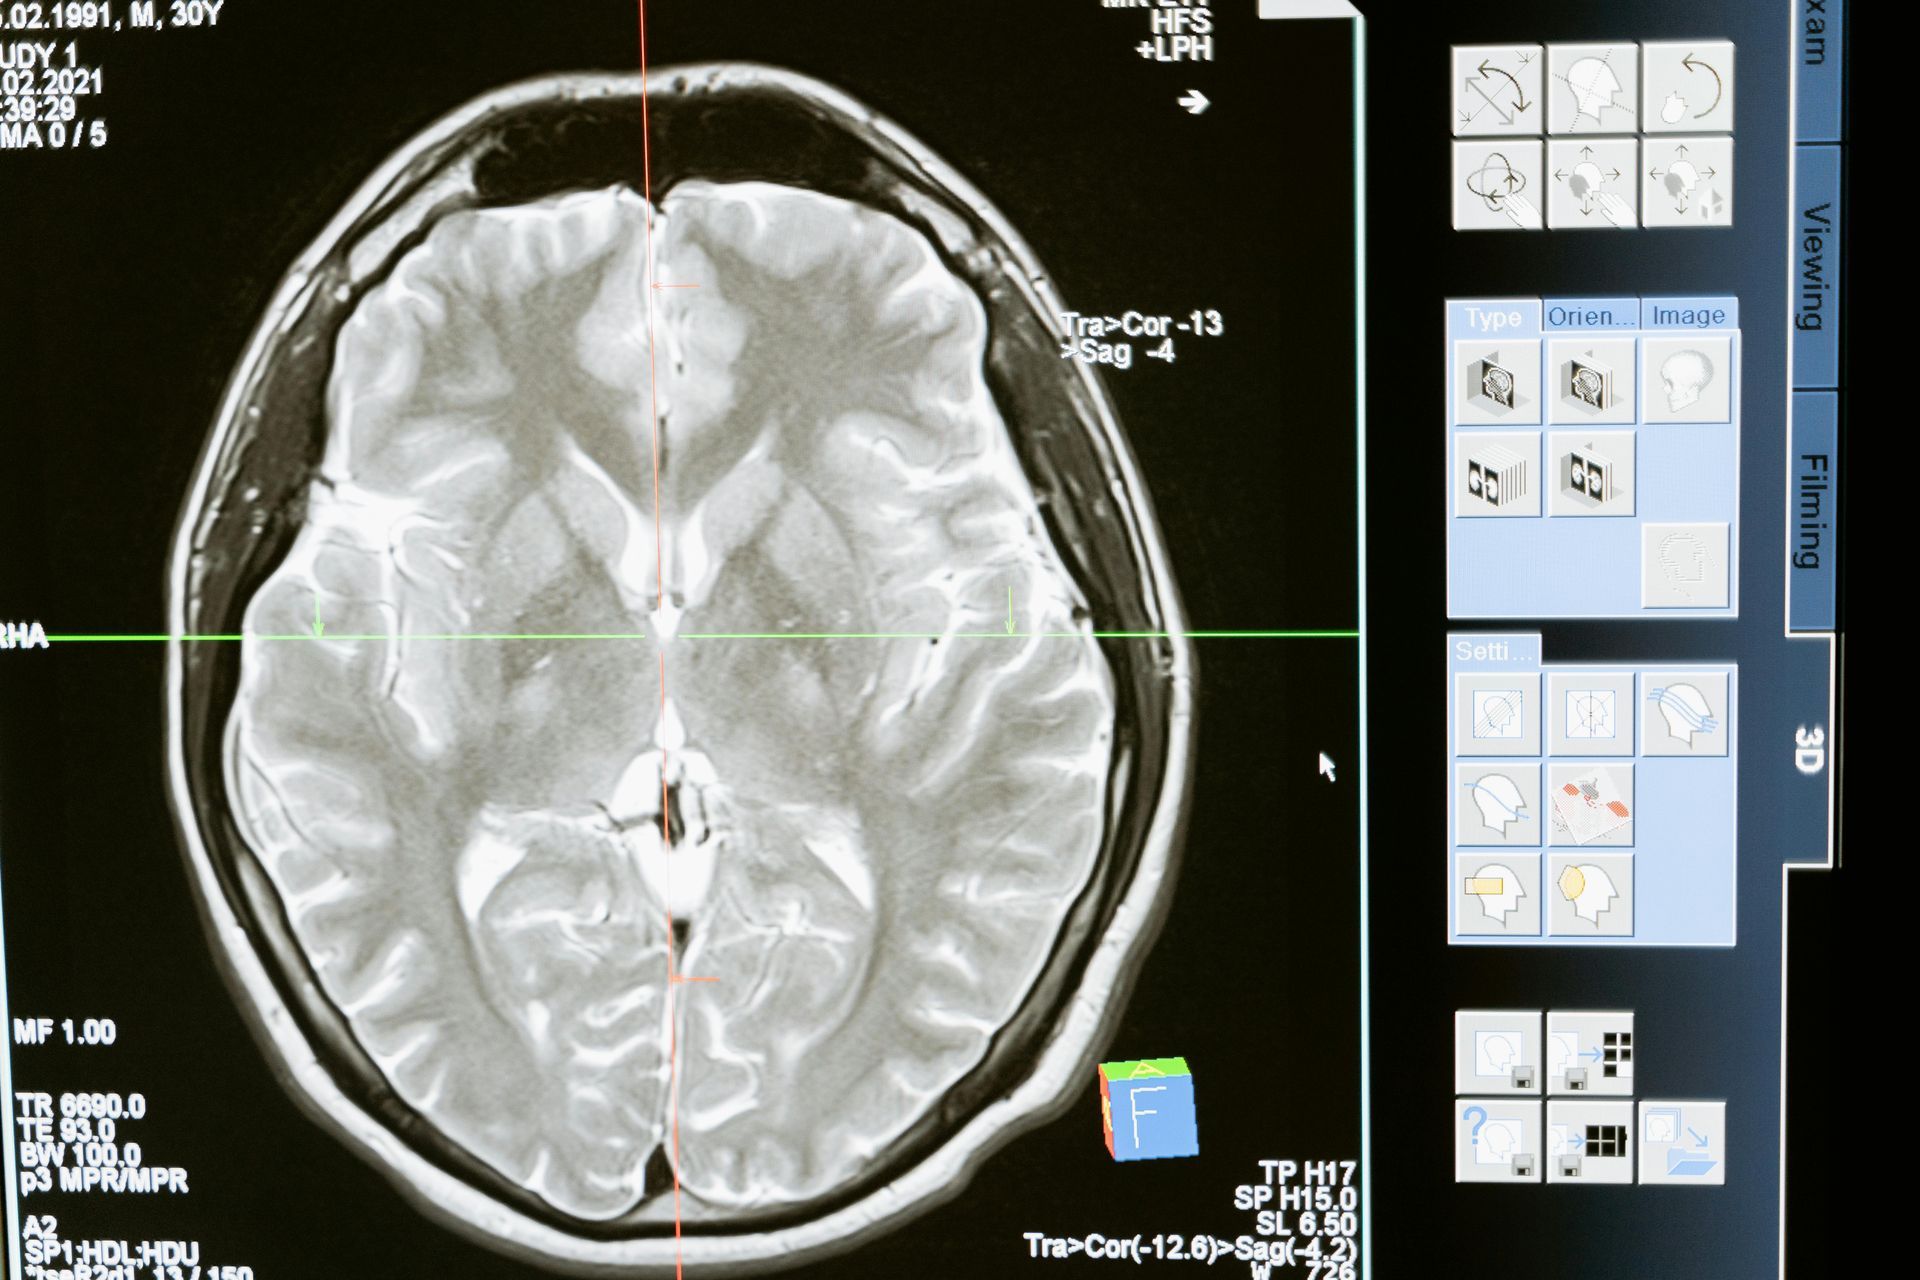

A traumatic brain injury (TBI) is one of the most devastating outcomes of an accident. Whether caused by a car crash, fall, sports incident, or assault, TBIs can affect every aspect of a person’s life—thinking, movement, emotions, and relationships. Recovery is often long, uncertain, and incredibly expensive. In many cases, life is never the same.

Brain injuries often involve delayed symptoms, unclear imaging results, and highly individual recovery outcomes. Insurance companies may try to downplay the seriousness of your injury—especially if it doesn’t show up on a standard scan. That’s why TBI cases require medical nuance, expert input, and a legal team with experience in serious injury litigation.